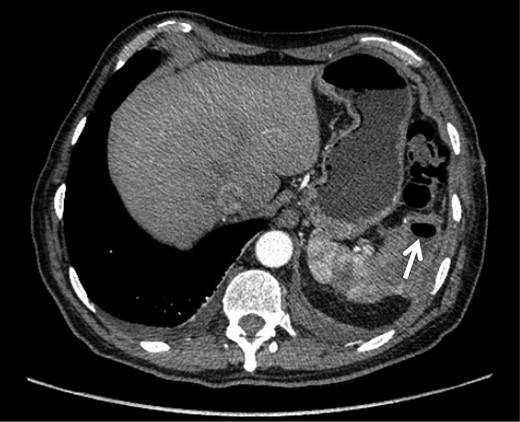

On admission, physical examination revealed normal vital signs and decreased breath sounds over the right pulmonary base as well as diffuse abdominal tenderness that was worse over the left hypochondrium. Blood culture samples as well as a complete blood count that revealed a normal hemoglobin and white cell count were taken. A CT scan confirmed the previously mentioned findings (Fig. 1). The patient was started on the same i.v. antibiotics he had been receiving (meropenem) and then taken to the operating room (OR) for video-assisted thoracoscopic lung decortication/pleurectomy. General surgery was then asked to assess the splenic abscess and, in consultation with interventional radiology, chose to treat conservatively. Two days later, the antibiotic regimen was simplified to i.v. ertapenem. After 4 days of this management, a new CT showed that the abscess had grown in size and had gas within it (Fig. 2). The decision was made to take the patient to the OR for a laparoscopic splenectomy.

CT scan taken on admission showing. (A) left-sided pleural effusion with empyema and septal loculations and (B) a subcapsular splenic abscess of approximately 5 cm × 2 cm × 3 cm with an approximate volume of 14 cc.